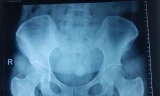

Ngày 9/5, thông tin từ Bệnh viện (BV) Quận 2 cho biết ê-kip của BV vừa phối hợp hỗ trợ với bệnh viện huyện Nhơn Trạch (Đồng Nai) cứu sống nam bệnh nhân M.V.C (sinh năm 1989) nguy kịch do thanh sắt rơi trúng bụng.

“Khoảng 20 phút sau, ê-kip gây mê hồi sức đã có mặt tại BV huyện Nhơn Trạch.  Sau đó lãnh đạo bệnh viện chúng tôi cũng cử thêm đội ngũ bác sĩ phẫu thuật của khoa Ngoại tổng quát  cùng đến hỗ trợ. Nhận định đây có thể là trường hợp xuất huyết tạng rỗng do chấn thương nên khi huyết áp và sinh hiệu bệnh nhân ổn định, các BS đã nhanh chóng vừa mổ cấp cứu vừa hồi sức cho người bệnh. Khi mổ  phát hiện khoảng 3 lít máu trong bụng. Bệnh nhân bị vỡ một đoạn ruột non dài và chảy máu sau phúc  mạc nên chúng tôi đã tiến hành cắt đoạn ruột bị giập, tạo hậu môn tạm và đưa ruột ra ngoài. Ca phẫu thuật diễn ra  Sau đó bệnh nhân đã được đưa về BV Quận 2 để tiếp tục theo dõi”, BS Minh nói.

Các BS cho biết sáng nay bệnh nhân C có xuất hiện tình trạng rối loạn đông máu và suy thận cấp do mất máu nhiều nhưng đã được kiểm soát kịp thời. Hiện sức khỏe bệnh nhân đã ổn định và sẽ được tiến hành thêm một cuộc phẫu thuật đóng hậu môn tạm trong thời gian tới.